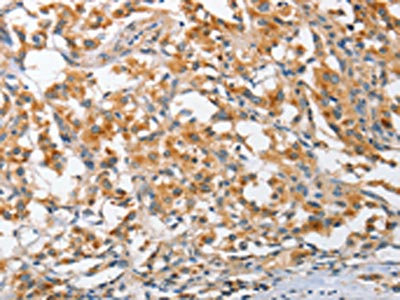

The image on the left is immunohistochemistry of paraffin-embedded Human thyroid cancer tissue using CSB-PA919511(ARL8A Antibody) at dilution 1/25, on the right is treated with fusion protein. (Original magnification: ×200)

The image on the left is immunohistochemistry of paraffin-embedded Human liver cancer tissue using CSB-PA919511(ARL8A Antibody) at dilution 1/25, on the right is treated with fusion protein. (Original magnification: ×200)